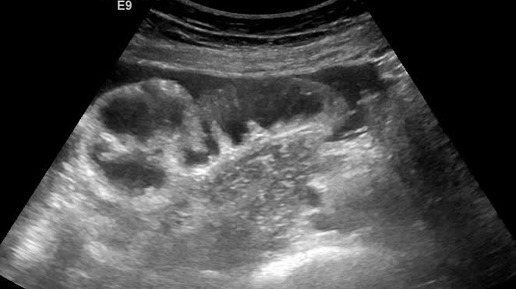

Видео к статье: "Свободная жидкость в брюшной полости"https://dzen.ru/a/Z-1KdOK-KyrjRiGF

Ультразвуковые находки от врача УЗД Зорина Я.П.